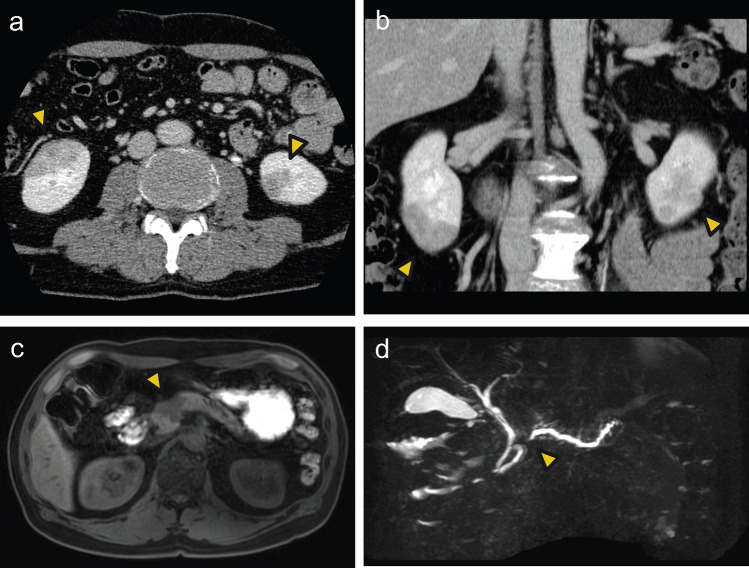

Membranous nephropathy (MN) is a common cause of adult-onset nephrotic syndrome. It is also known as a minor but established renal manifestation of Immunoglobulin G4-related disease (IgG4-RD). Previous reports suggest that MN can also be an initial manifestation of IgG4-RD, all of which are phospholipase A2 receptor (PLA2R)-negative MN. We describe a case of PLA2R-positive MN that subsequently developed other manifestations of IgG4-RD. A 60-year-old male with nephrotic syndrome was diagnosed as primary MN with positive staining for PLA2R on the initial renal biopsy, which remained in partial remission with supportive therapy using angiotensin II receptor blocker (ARB) without steroid. About 1 year later, a renal mass was detected during an annual checkup, and contrast-enhanced computed tomography revealed low-density masses in bilateral kidneys and the head of the pancreas. The findings of endoscopic biopsy of the pancreatic mass were consistent with autoimmune pancreatitis (AIP) and the second renal biopsy showed the findings of MN with tubulointerstitial nephritis, both of which led to a diagnosis of IgG4-RD. The second renal biopsy also showed positive PLA2R. The patient received oral glucocorticoid therapy for IgG4-RD, which improved IgG4-related AIP and renal masses and also resulted in complete remission of MN. To our knowledge, this is the first reported case of PLA2R-positive MN with subsequent development of IgG4-RD. It is sometimes difficult to determine whether PLA2R-positive MN occurring with IgG4-RD is primary MN or secondary MN associated with IgG4-RD. The possibility of developing IgG4-RD should be considered even when preceding MN is PLA2R-positive, suggesting of primary MN.